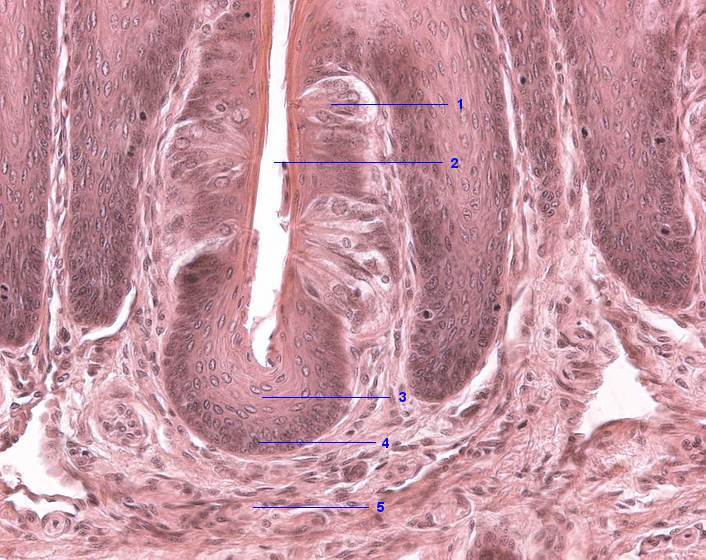

1 Geschmacksknospe

2 Papillengraben

3 Mehrschichtiges Plattenepithel, Str. spinosum

4 Stratum basale

5 Lamina propria